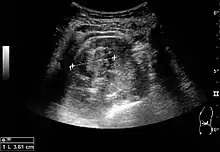

Cortical solid mass, which later was shown to be renal cell carcinoma. Measurement of the solid mass on the US image is illustrated by ‘+’ and a dashed line.[3]

Renal cell carcinoma with both cystic and solid components located in the cortex. Measurement of tumor on the US image is illustrated by ‘+’ and a dashed line.[3]

On renal ultrasonography, a solid renal mass appears in the US exam with internal echoes, without the well-defined, smooth walls seen in cysts, often with Doppler signal, and is frequently malignant or has a high malignant potential. The most common malignant renal parenchymal tumor is renal cell carcinoma (RCC), which accounts for 86% of the malignancies in the kidney. RCCs are typically isoechoic and peripherally located in the parenchyma, but can be both hypo- and hyper-echoic and are found centrally in medulla or sinus. The lesions can be multifocal and have cystic elements due to necrosis, calcifications and be multifocal (Figure 8 and Figure 9). RCC is associated with von Hippel–Lindau disease, and with tuberous sclerosis, and US has been recommended as a tool for assessment and follow-up of renal masses in these patients.[3]